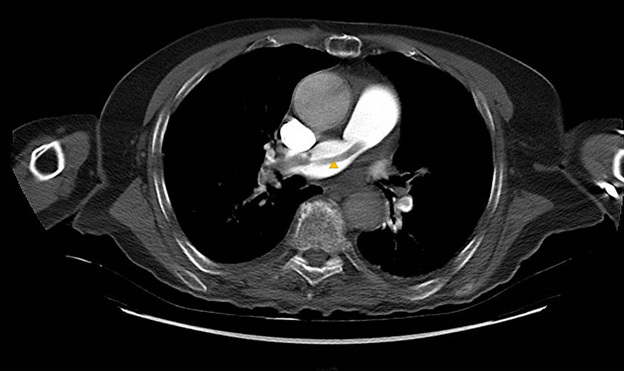

Findings in acute PE include both direct and indirect evidence of injury. Direct evidence of PE includes central filling defects within affected vessels surrounded by contrast material (“polo mint” or “railway sign” appearance depending on the view) or the “saddle embolus” that extends bilaterally from the base of the pulmonary trunk bifurcation. A clot can be seen traversing from the main pulmonary artery to the right pulmonary artery noted by the arrow in Figure 3 (an axial view of a CTPA in this patient with a PE).

Figure 3. Axial View of a Computed Tomography Pulmonary Angiography of a Patient with Pulmonary Embolism |

![]() |

A clot can be seen traversing from the main pulmonary artery to the right pulmonary artery. Courtesy of Jimmy Truong, DO. |

Indirect evidence of PE includes pulmonary infarction (wedge-shaped peripheral opacities) and pleural effusions seen on imaging. CTPA additionally can provide evidence of the severity of a PE if it detects evidence of right heart strain, significant clot burden, and decreased lung perfusion, all of which help with appropriate treatment and disposition of the patient.22 In addition to its high sensitivity and specificity in the diagnosis of PE, CTPA can provide additional evaluation of other potential diagnoses that remain on the differential. It is a strong test for assessing evidence of musculoskeletal injury, pericardial abnormalities, pneumonia, and other vascular pathologies (such as coronary artery disease) that may be causing various presenting symptoms.22